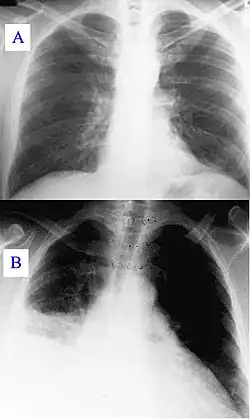

Основными методами диагностики являются рентгенологическое исследование лёгких и исследование мокроты, основным методом лечения — антибактериальная терапия. Поздняя диагностика и задержка с началом антибактериальной терапии ухудшают прогноз заболевания. В некоторых случаях возможен смертельный исход.

- Рентгенография грудной клетки